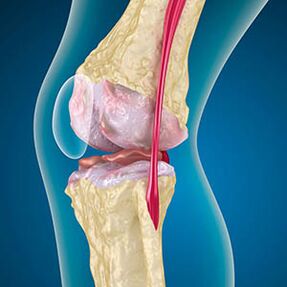

Στην περίπτωση της οστεοαρθρίτιδας, ο χόνδρος που ευθυγραμμίζει τις άκρες των οστών είναι τριβή ή λείπει. Ο κατεστραμμένος ιστός δεν αποτελεί πηγή πόνου επειδή δεν έχει υποδοχείς. Η φλεγμονή στις κοντινές δομές προκαλεί χαρακτηριστικά συμπτώματα.

Το σώμα συνεχίζει την αναγέννηση των κατεστραμμένων ιστών, αλλά ο χόνδρος αυξάνεται άνισα. Ως αποτέλεσμα, σχηματίζονται παρατυπίες που παραβιάζουν άλλα στοιχεία της άρθρωσης. Ο τύπος οστεοφυτών δηλώνεται ομαλός αρθρικός χόνδρος με αντιστάθμιση. Μια άλλη έκδοση δείχνει ότι η ανάπτυξη του "Spurs"Συσχετίζεται με την προσπάθεια σταθεροποίησης της άρθρωσης στα μέσα ή πλευρικά λόγω της αποδυνάμωσης των μυών.